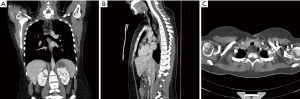

A previously healthy 19-year-old female was referred from a regional hospital in October 2009 with progressive dysphagia and a retrosternal tumour. She did not have significant weight loss. In computed tomography the lesion measured 4.9 cm × 3.5 cm × 9.0 cm (Figure 1). In the imaging, the tumour appeared heterogenic, located above carina, and was submucosal in oesophagus. In order to obtain a biopsy, both bronchoscopy and esophagoscopy were done under general anaesthesia. External compression of the oesophagus was noted between 12 to 25 cm from the incisor line and the mucosa was macroscopically normal. Several fine needle aspirations from the tumour were taken, which were all negative for malignant cells. In an oesophageal ultrasound examination cystic structures were identified, and the tumour appeared benign in nature. Operative treatment was scheduled, but due to patient-related factors, the operation was postponed to September 2010. Operative treatment consisted of a neck incision to approach the oesophagus, which was then encircled and muscular wall was opened vertically keeping the mucosa intact. The tumour was identified between muscle and mucosal layer and a pericapsular enucleation was performed (Figure 2). The patient was discharged on the second postoperative day without any primary complications. On a follow-up visit one month later the patient complained hoarseness and a consultation was appointed at the Department of Otolaryngology-Head and Neck Surgery. Left vocal cord paralysis was noted and scheduled for follow-up. During the first 1-year follow-up, her hoarseness subsided without any intervention and the patient has remained also otherwise symptomless.